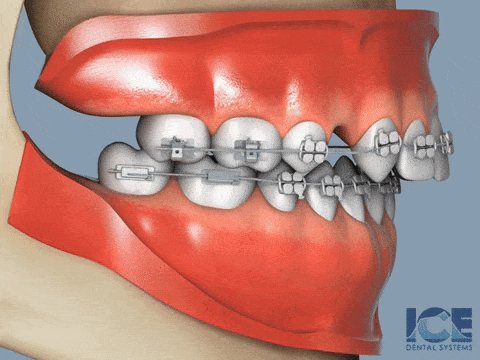

TAD is a tiny screw, a temporary implants that help achieve movement that braces alone cannot.

Especially important for Asians because our facial bones are often too small to fit all our teeth.

At Kuo Dental, we know how and when to use TADs to create smiles that fit your face perfectly.

Metal braces should aim to complete in 1-3 years. The longer the treatment, the higher the risk of root resorption (teeth getting shorter).

Without TADs, your teeth may eventually reach there, but it will take you much longer to complete your smile correction.